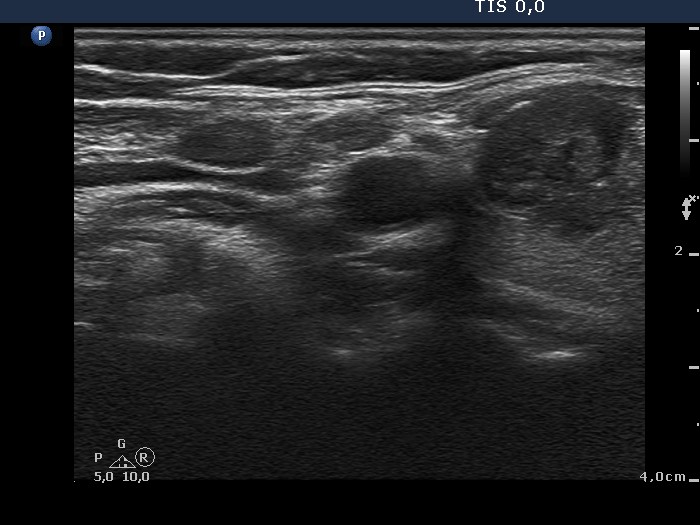

Ultrasonography: there was a moderately hypoechogenic nodule with irregular borders and combined type 2 and type 3 vascular patterns in the lateral part of the right thyroid. There were two lymph nodes above the right thyroid.